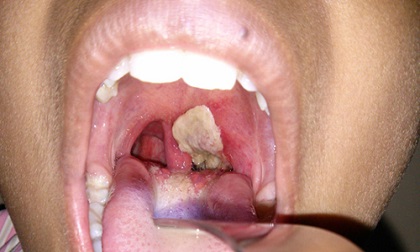

Một trường hợp tử vong vì bệnh bạch hầu vừa xảy ra tại tỉnh Quảng Ngãi. Đó là em Đinh Văn Huyền, 14 tuổi, ở xã Sơn Bua, huyện Sơn Tây.

Cách đây khoảng 3 tuần, Huyền phát bệnh, được người nhà đưa đến điều trị tại Bệnh viện Đa khoa tỉnh Quảng Ngãi nhưng bệnh trở nặng nên được chuyển ra Bệnh viện Phụ sản - Nhi Đà Nẵng.

Do bệnh nặng, Huyền đã tử vong sau đó. Kết quả xét nghiệm của Viện Pasteur Nha Trang cho thấy, bệnh nhân này dương tính với vi khuẩn bạch hầu.